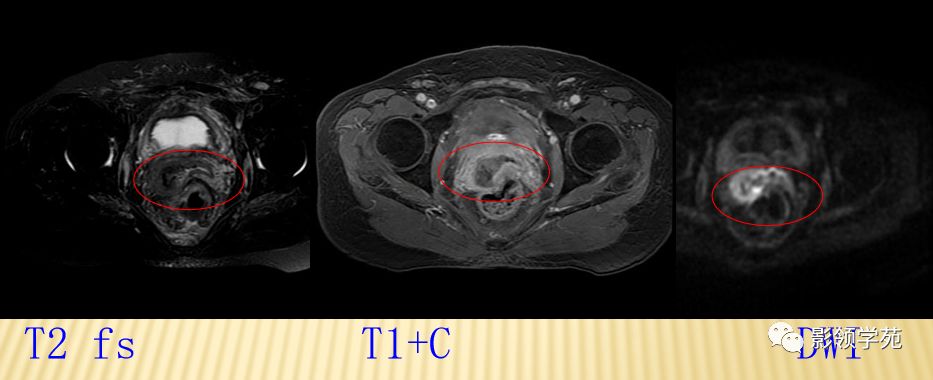

宫颈癌术后复发患者,DWI上病灶较T2 fs及T1+C更加明显

DWI:局限性高信号,癌组织ADC值<癌旁组织<小于正常宫颈组织

磁共振动态增强在宫颈癌中的应用

DCE-MRI是一种无创性功能成像方法,利用静脉注射对比剂的同时行连续多层扫描,以获得组织或肿瘤增强的时间-信号曲线(TDC),直接从毛细血管水平反映肿瘤内血流动力学变化,获得肿瘤灌注和毛细血管通透性等参数。

动态增强时间信号曲线

- 恶性肿瘤的动态增强模式多数为早期快速强化后缓慢减低或早期强化后持续强化出现“平台期”;

- 良性肿瘤或正常组织多表现为缓慢持续强化或无强化。

- 对宫颈癌的动态增强研究显示为“速升缓降型,或速升速降型”,动脉早期即明显强化,强化程度高于子宫肌层及宫颈基质,其达峰时间为注射造影剂后30~60 S。静脉期及延迟期逐渐廓清,至延迟期信号强度低于周围基质。